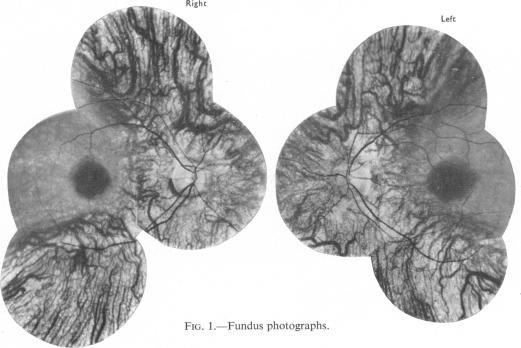

RETINOPATHY DURING CHLOROQUINE THERAPY.

Br J Ophthalmol. 1961 Nov;45(11):756-8. doi: 10.1136/bjo.45.11.756.